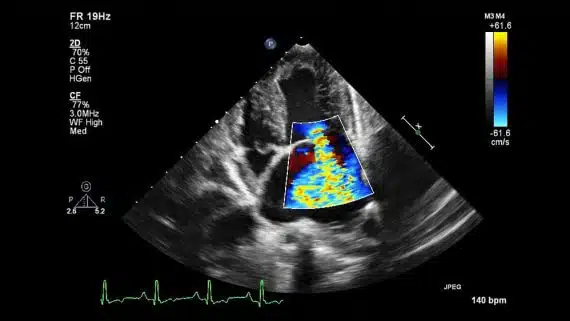

تخطيط صدى القلب الدوبلر الملون

تُستخدم هذه الطريقة لتقييم و قياس تدفق الدم عبر صمامات و غرف القلب. حيث تعتبر كمية الدم التي تضخ مع كل نبضة من نبضات القلب المؤشر على عمل القلب. يمكن أيضاً لمخطط صدى القلب ( إيكو القلب ) الدوبلر اكتشاف تشوهات تدفق الدم داخل الحاجز القلبي.